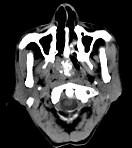

问题 男性,57岁,睡觉打鼾,近来加重,CT扫描如图所示,请选择正确的描述和答案()

选项 A.鼻咽腔偏右侧可见类圆形软组织块影 B.肿块内密度尚均匀,其上方见较多钙化影 C.肿块边缘大部清楚,邻近结构未见明显受侵 D.考虑为鼻咽癌 E.考虑为鼻咽部多形性腺瘤

答案 ABCE